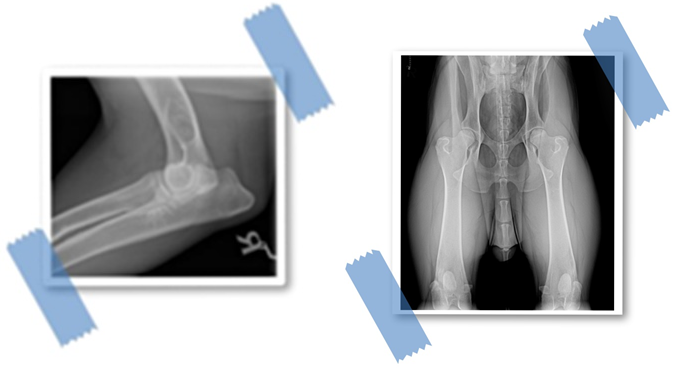

In unserer dritten Folge wollen wir uns mit der Hüftgelenks- und Ellenbogendysplasie (HD, ED)beschäftigen.